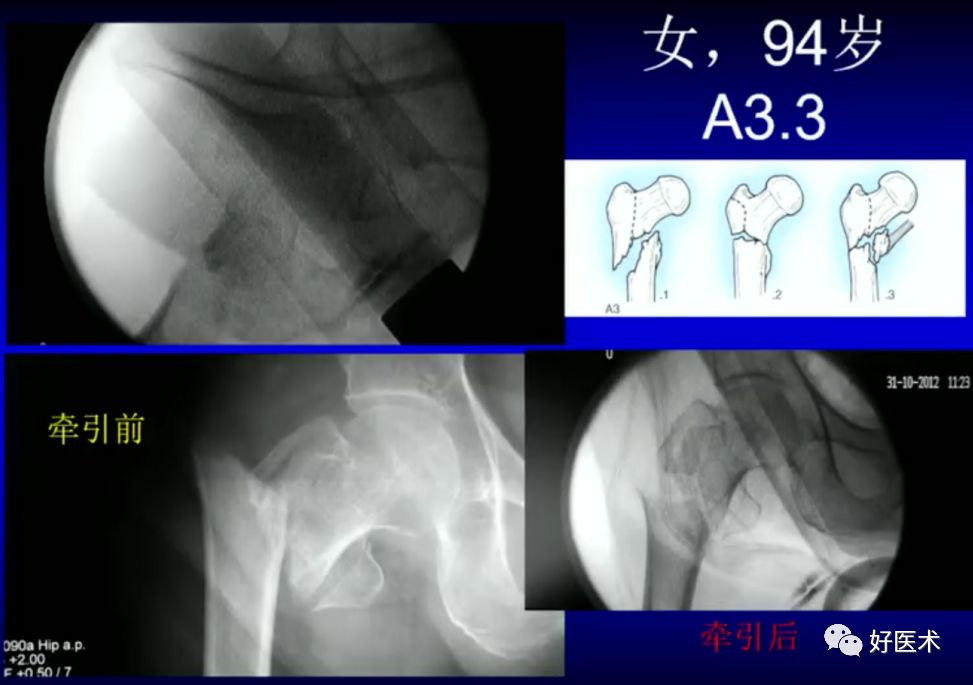

病例一:女 94岁

病例二:女 75岁

术前复位:

定位:

术后: